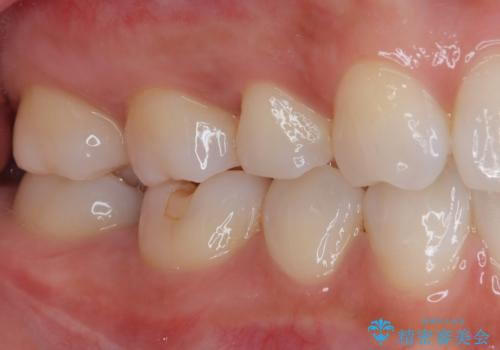

見た目、機能面共に大変喜んでいただきました。

歯と歯の間の虫歯をコンポジットレジンや保険のメタルインレーで治すと段差ができたりして清掃性が悪くなるので、セラミックインレー修復やゴールドインレー修復などの適合の良い詰め物で治療することをオススメします。